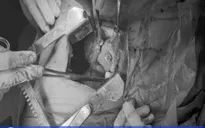

Bệnh nhân bị rách động mạch chủ bụng, vết thương bó mạch thượng vị dưới chảy nhiều máu, khó cầm, gây nhiều khó khăn trong quá trình phẫu thuật. Ngoài ra, còn có thủng ruột non. Vị trí tổn thương nằm sau các tạng quan trọng, dễ gây tổn thương các tạng xung quanh trong quá trình phẫu thuật. Kíp phẫu thuật đã nhanh chóng khâu cầm máu các tổn thương.

Sau hơn 3 giờ đồng hồ, ca phẫu thuật thành công. Bệnh nhân đã được truyền 2 đơn vị máu. Hiện tại tình trạng bệnh nhân ổn định, tiếp tục được truyền máu, theo dõi và điều trị tích cực.